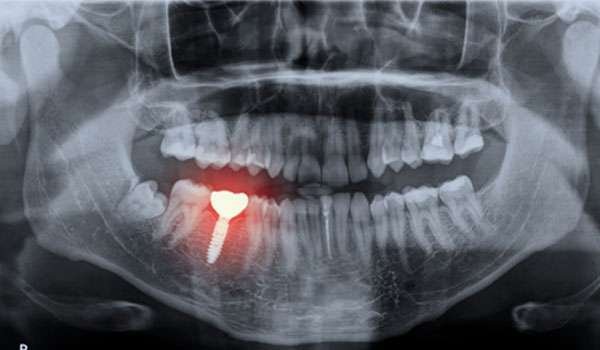

OPG, or Orthopantomogram, is a panoramic scanning dental X-ray of the upper and lower jaw. It provides a wide view of the jaw and teeth, capturing detailed images of the mouth, including the teeth, jawbones, and surrounding structures, in a single, comprehensive image. This technology is instrumental in diagnosing various dental conditions and planning treatments effectively.

• Comprehensive Diagnosis: OPG provides a complete view of your oral structures, enabling our dentists to detect issues such as impacted teeth, jaw fractures, and bone abnormalities.

• Treatment Planning: The clear, comprehensive images facilitate precise treatment planning for procedures such as orthodontics, implants, and oral surgery.